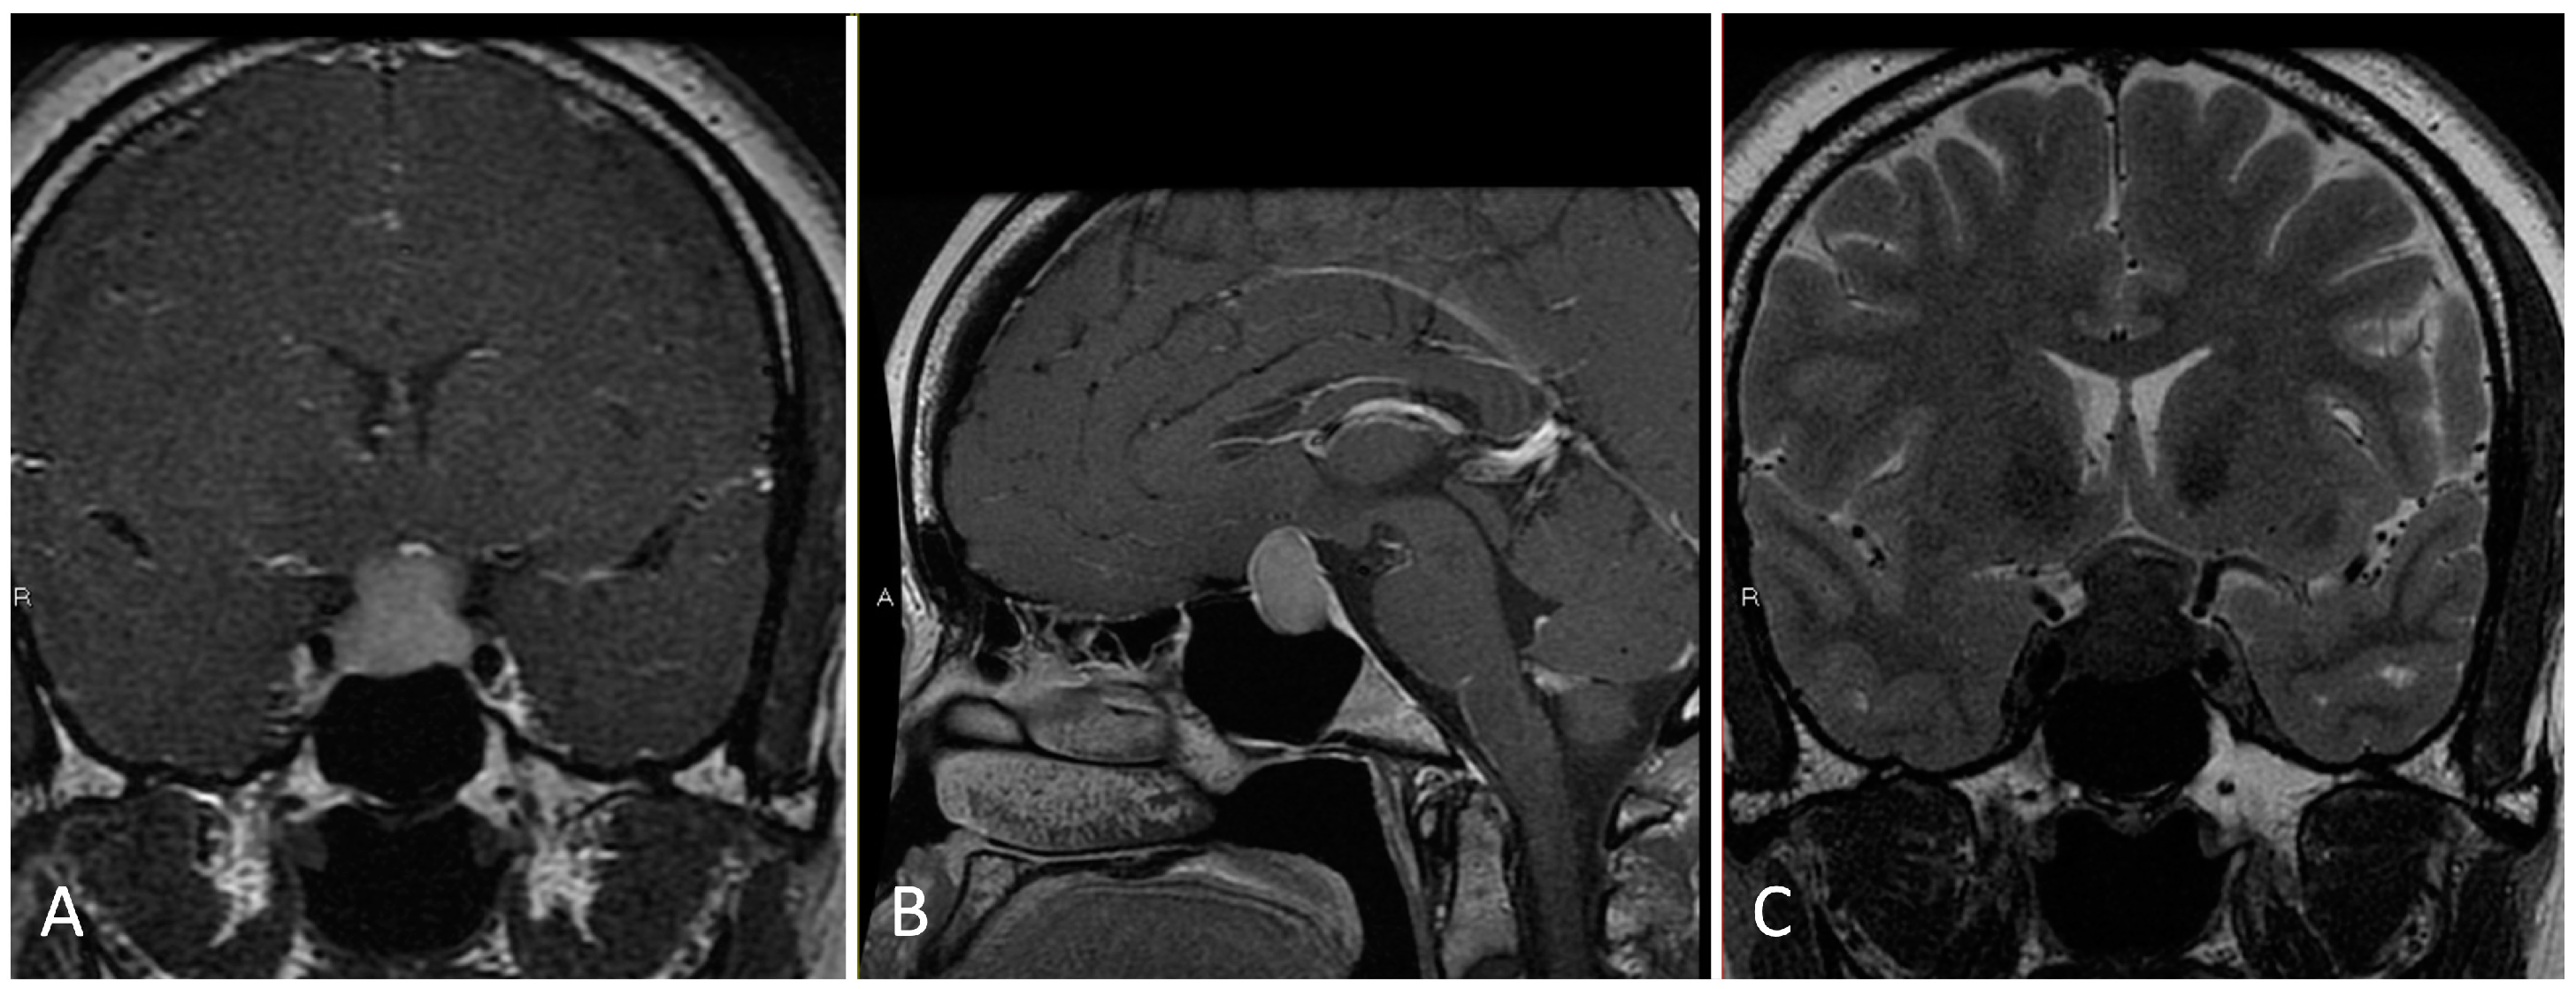

3.1.2. Illustrative Case

- Dural opening of Rathke’s cleft cysts, one should begin anteriorly and inferiorly to minimize the risk of inadvertent CSF leak and iatrogenic injury to the pituitary gland.

- One must be mindful of diaphragm downward migration and identification during cyst resection to avoid a CSF leak.